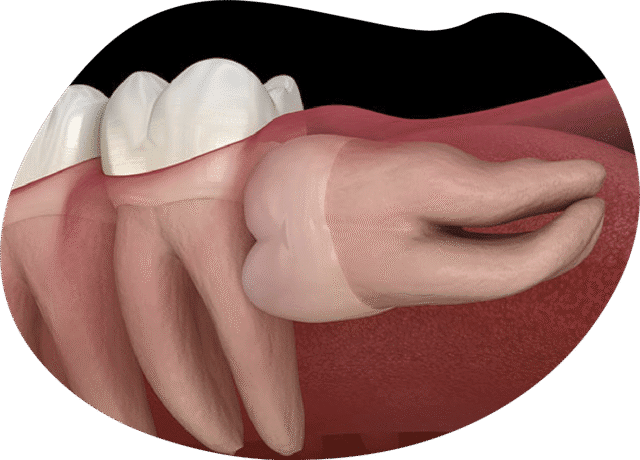

The Role of Expertise and Technology

Advanced surgical training, digital imaging, and modern protocols improve safety and success. These investments affect pricing but also protect patients from complications such as:

• Infection

• Nerve damage

• Long-term pain

• Repeat surgeries

Patients should view cost as an investment in safety.